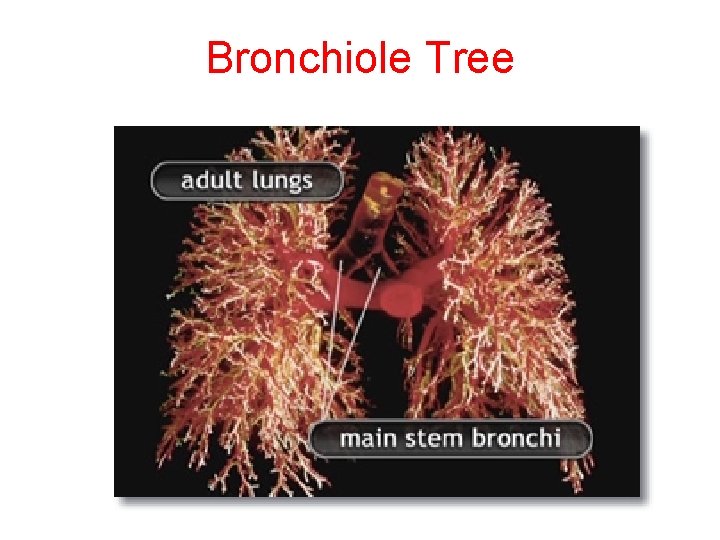

Bronchiole Tree

Bronchiole Tree